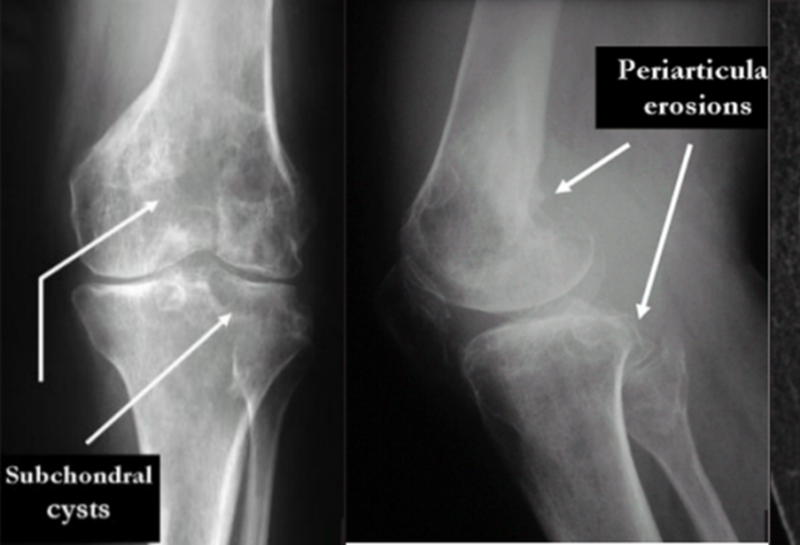

【影像学表现】早期、中期的PVNS患者,X线表现多无特异性。晚期X线下可表现为骨侵蚀,软骨下骨囊肿等。X线的早期诊断意义较低。CT对腱鞘巨细胞瘤病变有早期诊断价值,尤其是骨质侵蚀破坏的范围与细节优于X线检查。CT检查也能显示关节积液、滑膜增厚和滑膜结节突起等,但对于软组织检查弱于MRI检查。MRI表现:由于此病含有多量含铁血黄素沉着,被吞噬细胞吞噬后,在细胞内产生T1弛豫时间增强效应,含量较高时,在T1和T2加权图像上均为低信号,这是本病在MRI上的特征性表现。